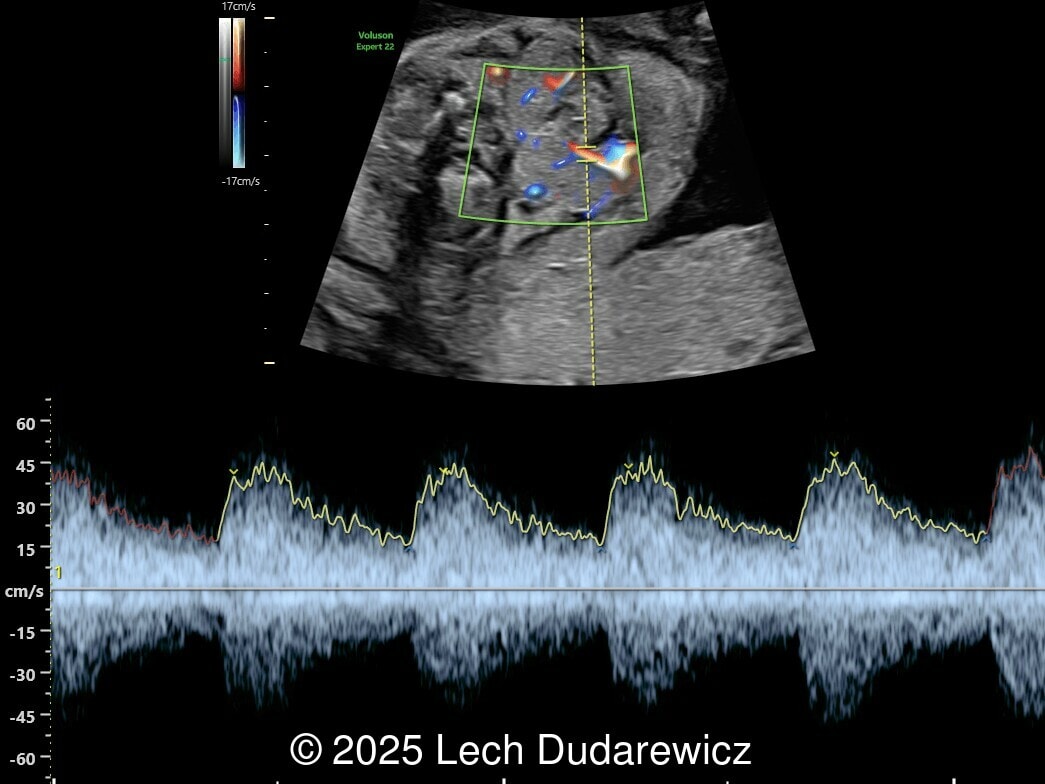

Image 2

We present a case of fetal hypothyroidism diagnosed at mid-trimester ultrasound.

Ultrasound images demonstrated a symmetrically enlarged thyroid gland that was isoechoic to slightly hyperechoic relative to the surrounding tissues. Color Doppler revealed peripheral hypervascularization of the thyroid, known as the “peripheral vascular rim sign”. No internal parenchymal hyperperfusion was noted. Amniotic fluid volume was within normal limits and no structural anomalies were observed in the remainder of the scan.

Prenatal ultrasound is the preferred method of screening for head and neck masses. The first ultrasound diagnosis of a fetal goiter was made by Weiner et al. in 1980 [11], and since then several cases have been published, mostly isolated or small series [12,13]. Ultrasound can accurately assess the size, location, internal blood supply, and growth of the fetal goiter, as well as evaluating its effects on neighboring structures and amniotic fluid volume. Key sonographic findings include a homogeneous, echogenic, symmetric mass in the anterior portion of the fetal neck corresponding to the thyroid enlargement (measurements above the 95th percentile for gestational age), polyhydramnios (not always present), and abnormal fetal neck contour [1]. On color Doppler evaluation, peripheral hyperperfusion ("peripheral vascular rim sign") supports the diagnosis of hypothyroidism with a hypertrophic but inactive thyroid gland. Diffuse parenchymal hyperperfusion (“thyroid inferno”), due to an overactive thyroid gland, is expected in hyperthyroidism [14,15]. Three-dimensional ultrasound may facilitate the parent’s understanding of the fetal goiter [16] and magnetic resonance imaging (MRI) can be useful for evaluating the compression and patency of the trachea and esophagus [17].

Fetuses of mothers with Graves' disease are at risk of developing either hypothyroidism or hyperthyroidism. In these patients, congenital goitrous hypothyroidism occurs due to the transplacental passage of antithyroid drugs or inhibitory immunoglobulins, while congenital hyperthyroid goiter occurs due to the passage of antibodies against the thyroid stimulating hormone receptor [1]. In both situations, the B-mode ultrasound findings are similar, making it difficult to use ultrasound alone to distinguish between the two conditions. Assay of thyroid hormones in the amniotic fluid does not strictly reflect fetal thyroid status and reference intervals are established only for the third trimester [18]. Therefore, fetal thyroid status can only be determined with certainty by fetal blood sampling through cordocentesis, which has a complication rate of approximately 1.4% to 2.0% [19]. In an attempt to avoid invasive methods, Huel et al. [20] described an ultrasound score to predict fetal thyroid function in cases of fetal goiter, based on the color Doppler pattern of the goiter, fetal heart rate, bone maturation, and fetal mobility. Accelerated bone maturation (typical of hyperthyroidism) is suggested by the presence of a distal femoral ossification center before 31 weeks, while its absence after 33 weeks indicates delayed bone maturation and hypothyroidism. Contrary to what happens in adult life, hyperthyroid fetuses show normal movement patterns, while jerky movements are observed in most hypothyroid fetuses.